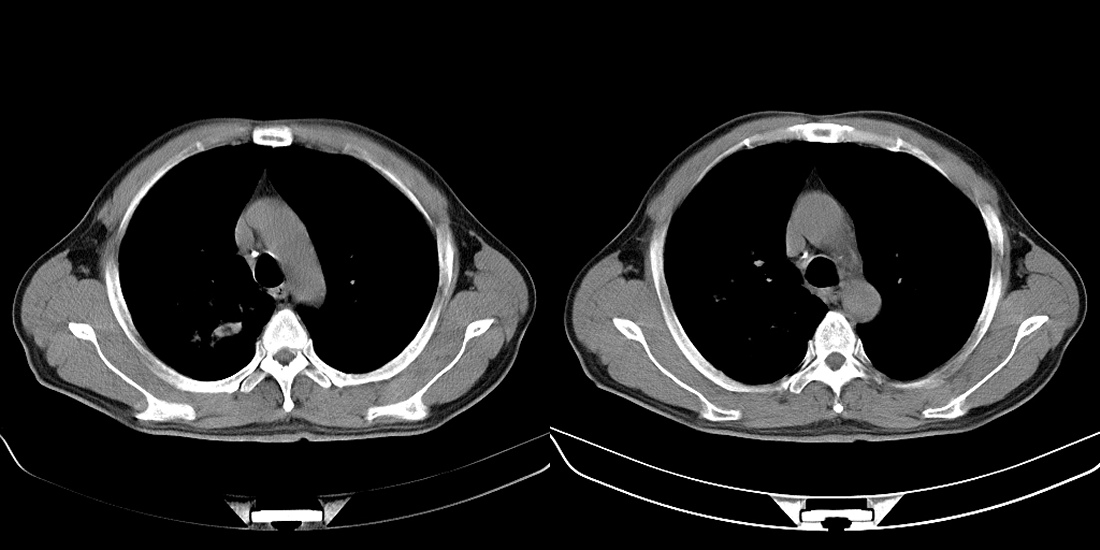

标题: CT10251:男性56岁,结核球? [打印本页]

标题: CT10251:男性56岁,结核球?

56岁男性,低热、消瘦,曾x线诊断肺结核。